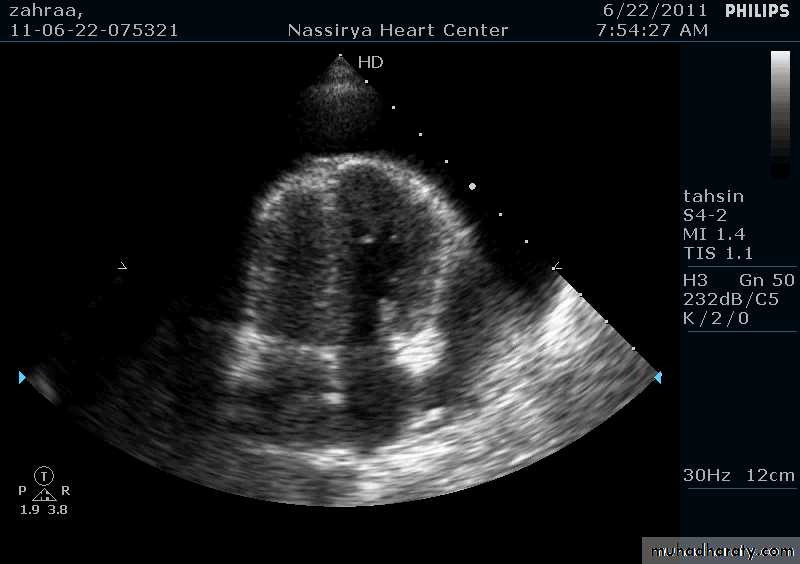

Pericardial Effusion: Investigation

Echocardiography: establishes the diagnosis31